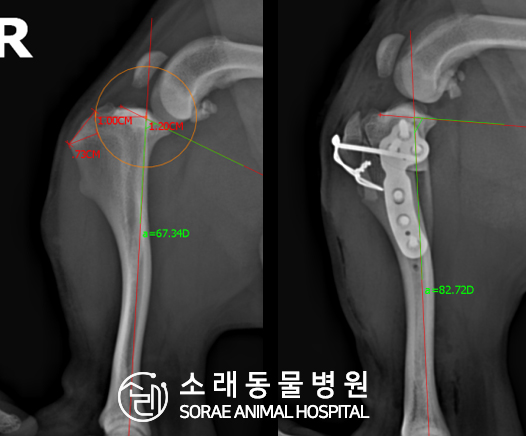

계산식으로 사전에 계획해두었던 플랜에 따라 경골을 절제하고

플레이트와 스크류를 사용하여 임플란트를 적용해 주었습니다.

반대 방향으로 밀려나 어긋나있던 대퇴골과 정강이가

제 자리를 찾으면서 무릎의 각도가 교정된 것을 확인할 수 있습니다